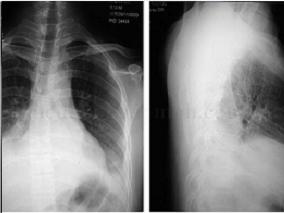

1小时条评论一、病史摘要 患者,男性,27岁,因反复咯血26天于2009年10月5日入院。患者于2009年9月9日修车时突然出现咯血,量约250ml(1~2次),鲜红色,无发热、咳嗽、咳痰、气促及胸痛等不适,就诊于当地县人民医院,胸片示右下肺不张(图120‐1),予以垂体后叶素等药物治...